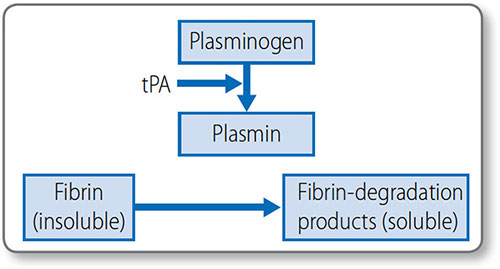

Thrombolysis (or fibrinolysis) is the process of cleaving insoluble fibrin into soluble degradation products, to remove clots (Figure 1.41). This limits thrombus size, allows remodeling and breaks the thrombus down once the causative damage has been repaired.

Cleavage is mediated by plasmin, which circulates as inactive plasminogen and is activated by tissue plasminogen activator (tPA). Endothelial cells release tPA in response to the presence of thrombin.

Figure 1.41: Mechanism of thrombolysis plasmin breaks down insoluble fibrin into soluble degradation products. tPA, tissue plasminogen activator.